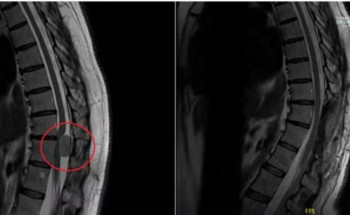

مركز جراحات المخ والأعصاب والعمود الفقري بمجمع الدكتور سليمان الحبيب بالعُليا يُعيد قدرة خمسينية على المشي مجدّداً

بفضل الله، نجح فريق متخصّص في مركز جراحات المخ والأعصاب والعمود الفقري بمجمع الدكتور سليمان الحبيب الطبي بالعليا، في استئصال ورمٍ كبيرٍ بالحبل الشوكي لسيدة في العقد الخامس، كان قد تسبّب لها في حدوث عدم ...